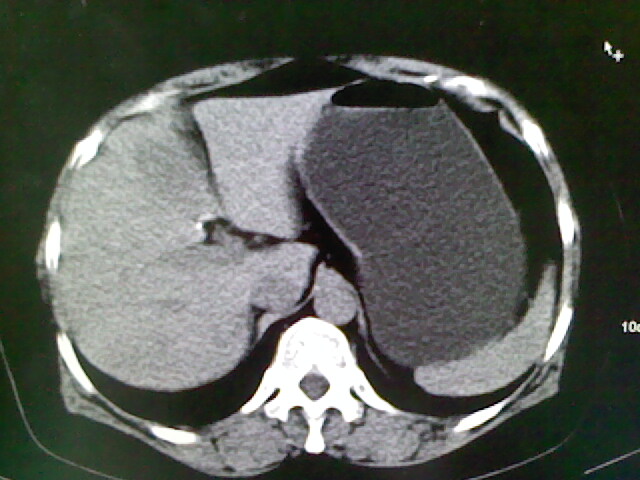

以下是引用卜一在2009-4-2 13:26:00的发言:[br]胆囊颈部结石伴胆囊炎!另:建议增强,待除外肝内占位及胆囊占位!

以下是引用liaoqiang在2009-4-2 16:23:00的发言:[br]胆囊是否切除?胆囊颈区致密影考虑金属夹?结石?肝脏右叶低密度影,考虑增强。